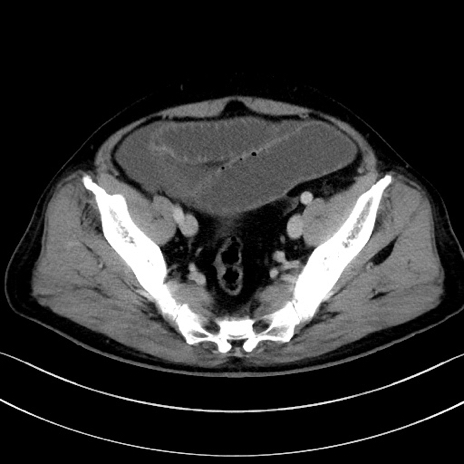

症例15(横断像)

【症例】70歳代男性

【主訴】腹痛

【現病歴】今朝から腹痛あり。全体的に痛い。特に左上の方。排ガスが今日はない。冷や汗が出る。

【既往歴】直腸癌術後

【身体所見】左側腹部〜上腹部に圧痛あり。腹膜刺激症状明らかなではない。軽度反跳痛。左下腹部に術後瘢痕あり。

【データ】WBC 7700、CRP 0.02